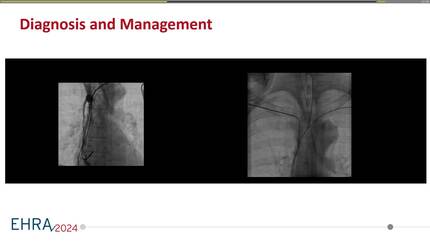

Permanent cardiac pacing in a patient on chronic renal dialysis with severe mitral stenosis, hypertrophic cardiomyopathy, superior vena cava occlusion and stenosis of the inferior vena cava